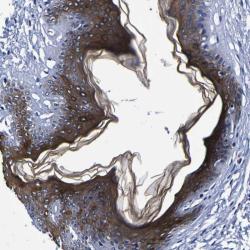

- Immunohistochemical staining of human skin shows strong cytoplasmic positivity in epidermal cells.

- Staining pattern partly consistent with experimental and/or bioinformatic data.